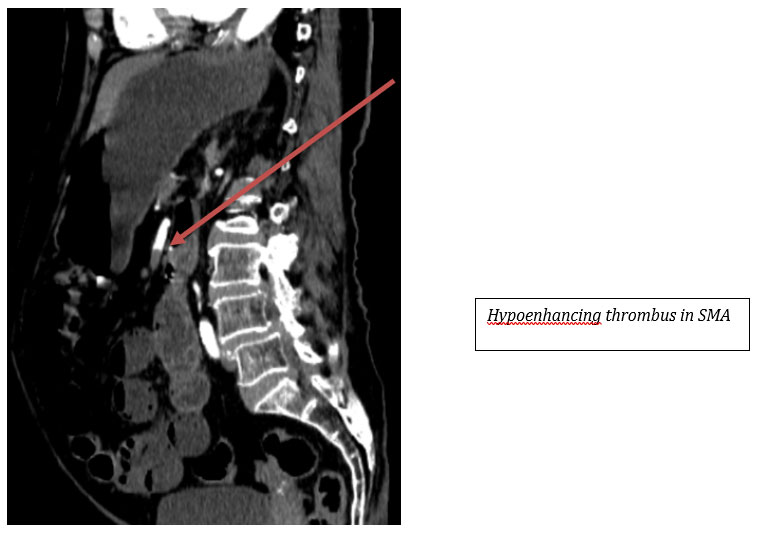

CECT Findings:

– Near‑complete occlusion of distal main trunk of the superior mesenteric artery (SMA).

– Hypoenhancing small bowel loops with intramural air pockets involving distal jejunum and proximal ileum — likely ischemic bowel.

Acute mesenteric ischemia is a critical diagnosis requiring prompt recognition. Elderly patients, particularly those with vascular risk factors, are vulnerable to SMA occlusion. Radiological findings such as hypoenhancing bowel, pneumatosis intestinalis, bowel dilatation, and vascular cutoff are key indicators of bowel ischemia. Early surgical intervention or endovascular management can significantly improve outcomes. This case underscores the role of CECT in detecting life‑threatening ischemia even in the absence of overt pneumoperitoneum.

Superior mesenteric artery occlusion leads to compromised perfusion of midgut structures. In elderly patients, thromboembolic disease is a common cause. CT features of established ischemia include poor bowel wall enhancement, intramural air, mesenteric fat stranding, and portal venous gas. Differentiating viable from non‑viable bowel is essential for guiding emergency management. Immediate revascularization and surgical assessment are crucial in preventing bowel infarction.